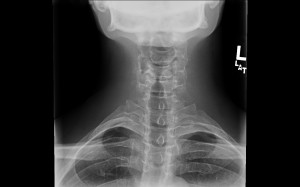

dolor cervical acupuntura girona